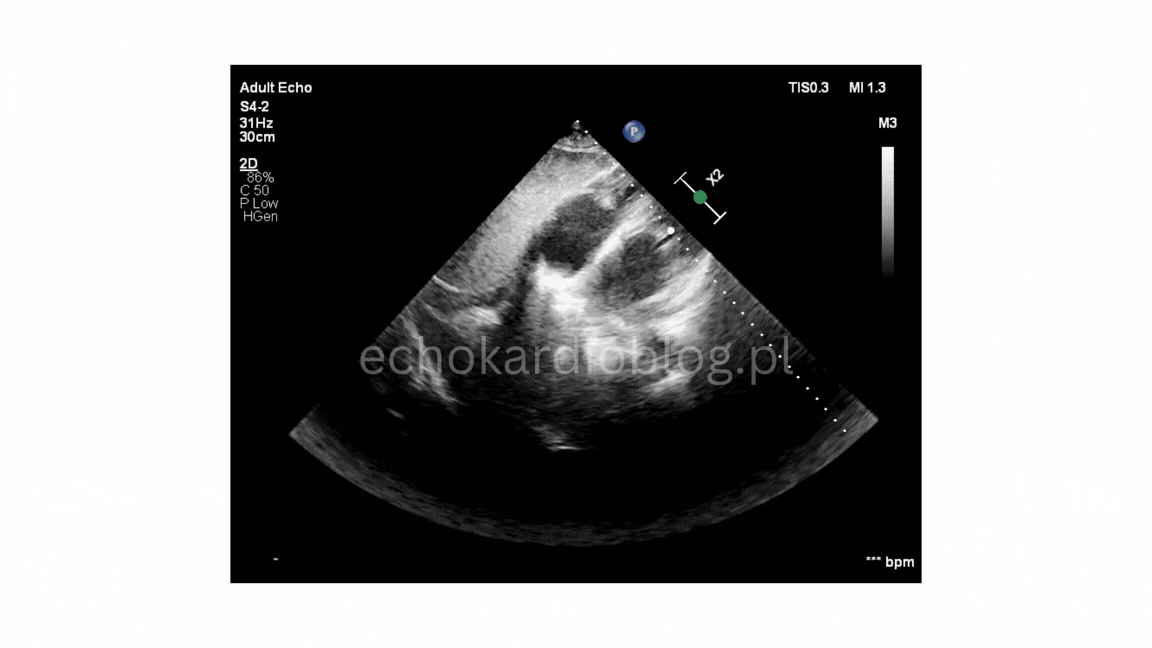

Pacjent , lat 66, przyjęty z podejrzeniem sepsy, w badaniu echokardiograficznym ujawniono duże, ruchome wegetacje na trzech zastawkach – mitralnej, trójdzielnej i płucnej . Wegetacje najlepiej widoczne były w projekcjach podmostkowych . Obraz jest dramatyczny: wysokie ryzyko powikłań zatorowych i przeciążenia prawego serca.

A 66-year-old patient admitted with suspected sepsis underwent echocardiography, revealing large, mobile vegetations on the mitral ,tricuspid and pulmonary valves .Vegetations were most clearly visualized in subcostal projections. The findings are dramatic, indicating a high risk of embolic complications and right heart overload.

w projekcji – podmostkowej 4 jamowej uwidoczniono wegetacje na zastawce trójdzielnej i mitralnej

projekcja podmostkowa 4 jamowa- umiarkowana niedomykalność trójdzielna